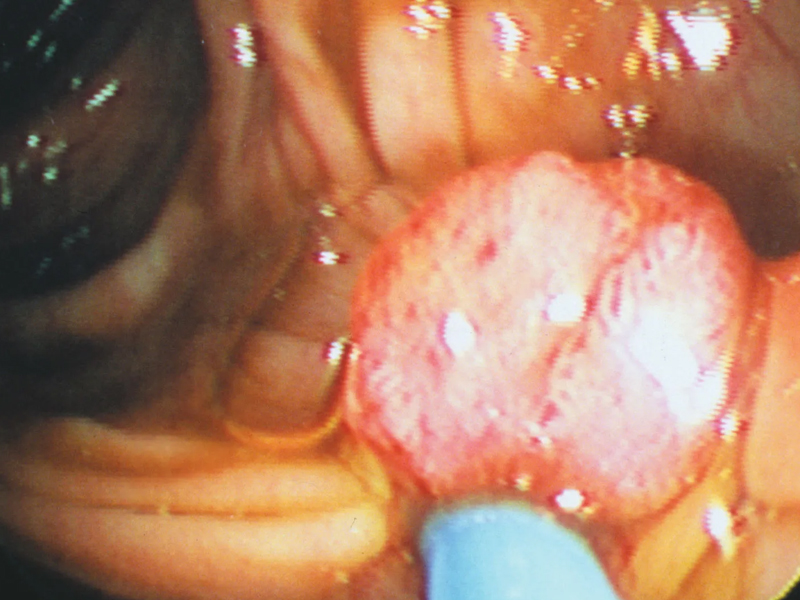

近日,哈醫大二院腫瘤中心結直腸腫瘤外科主任王貴玉教授團隊就收治了一對夫妻。 56 歲的王女士(化名)和丈夫李先生(化名),平時飲食喜歡吃高油、高熱量的食物。妻子王女士平時身體健康,然而最近幾個月卻出現了便血的情況,而且伴隨頭暈乏力等癥狀。當地醫院的腸鏡檢查結果顯示,在她的乙狀結腸部位發現了幾乎佔滿腸腔的惡性腫瘤。 ![]() 確診后,王女士在丈夫李先生的陪同下,來到哈醫大二院腫瘤中心。王貴玉教授詳細了解王女士的病情后,為其安排了全面的術前檢查,並將手術安排提上日程。 與此同時,李先生在陪同妻子治病的過程中頻繁出現乏力、腹痛等癥狀。王貴玉教授得知李先生的癥狀后,強烈建議他接受腸鏡檢查。檢查結果顯示李先生的升結腸處有一巨大腫物,經病理學檢查證實為惡性。 醫生先後為王女士及李先生進行了手術,手術過程十分順利。目前,夫妻二人已恢復了健康。 醫生告訴記者,夫妻同時患結直腸癌的情況較為罕見,這種情況的出現與夫妻間長時間的共同生活習慣相關。 ![]() 一是夫妻通常在一起進餐,共同的不良飲食習慣可能會增加結直腸癌發病風險。 二是夫妻可能有相似的不良生活習慣,如缺乏運動、吸煙或酗酒,這些習慣都會增加結直腸癌的發病風險。 三是夫妻共同面對生活中的壓力和心理因素,這可能影響他們的免疫系統和整體健康狀況,進而增加患上結直腸癌的風險。 |